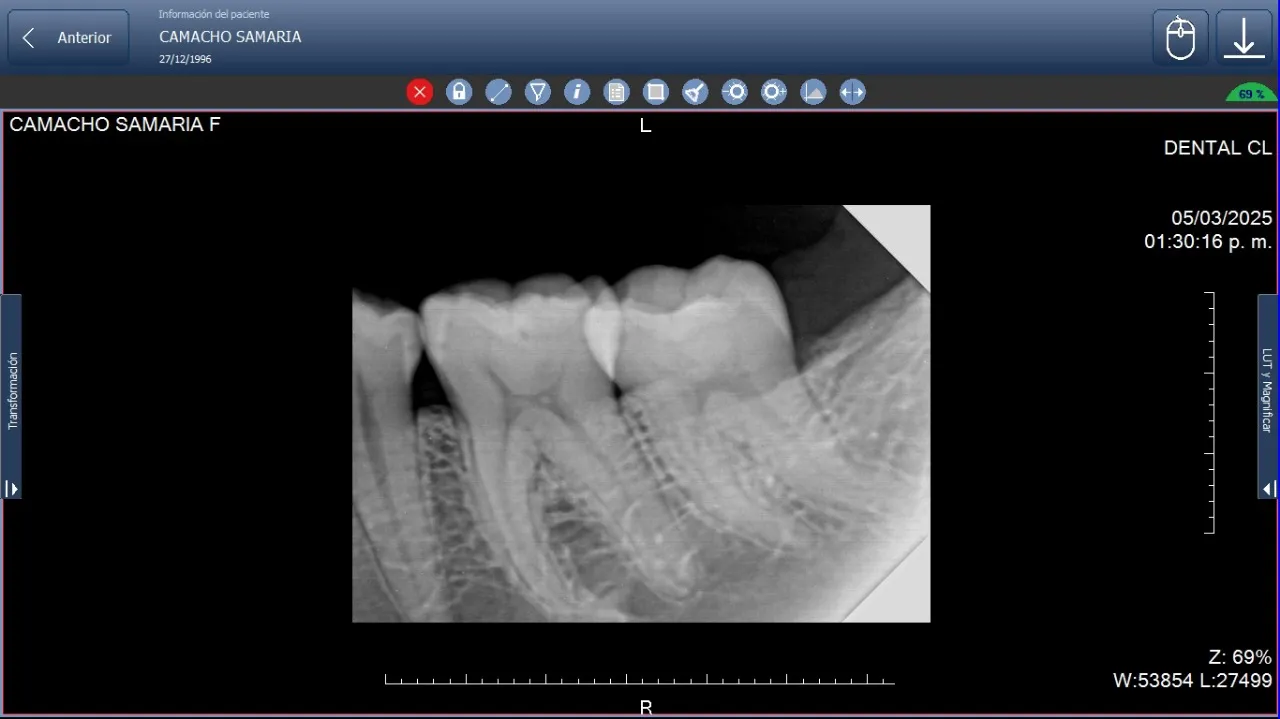

Radiografía periapical de alta calidad que facilita la identificación temprana de problemas dentales y óseos en diagnóstico clínico.

En odontología humana, la radiografía periapical se utiliza desde revisiones de rutina hasta cirugías complejas. Su capacidad para mostrar detalles finos la convierte en un apoyo constante para el profesional.

En veterinaria, este estudio es clave para evaluar piezas dentales en perros, gatos, aves y otros animales. Permite detectar fracturas, infecciones o problemas dentales que afectan directamente a la calidad de vida del paciente animal.

Control de implantes dentales

Es habitual realizar controles periódicos para verificar la estabilidad del hueso alrededor del implante y detectar problemas de forma temprana.